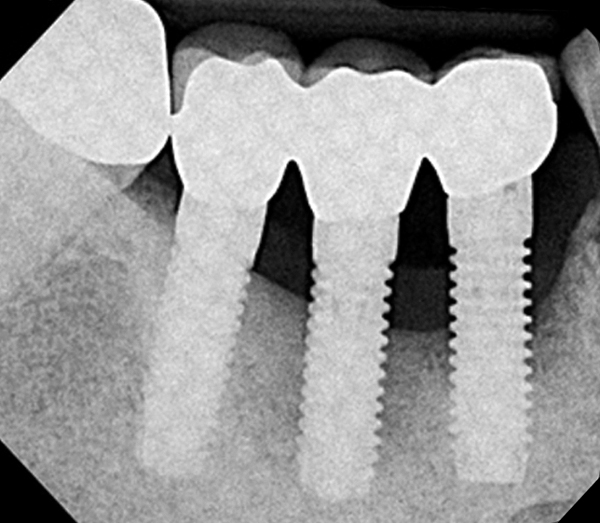

Millennium Dental Technologies: Helping Clinicians Stem the Tide of Failing Implants - Volume 34, Issue 8 - Compendium